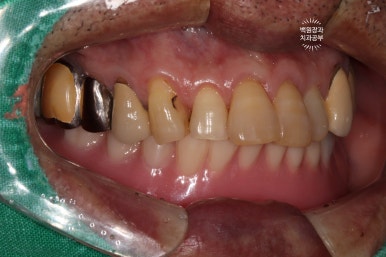

저희 치과에 내원하셨을 당시 입안 사진입니다.

사실 사진만으로는 그 불편함을 느끼기가 어려우실텐데요, 아래는 비교적 최근에 제작된 깔끔한 전체틀니를 사용하고 계셨고, 위 어금니는 만성치주염에 이환되긴 했지만 형태를 모두 갖추고 있었습니다.

아래턱 전체틀니는 무지하게 잘 떨어집니다.

틀니접착제를 사용해도 마찬가지죠..

위턱 치아들은 그렇다치고...

아래턱에 사용하고 계신 전체틀니에 매우 불만족하고계신 상태였습니다.